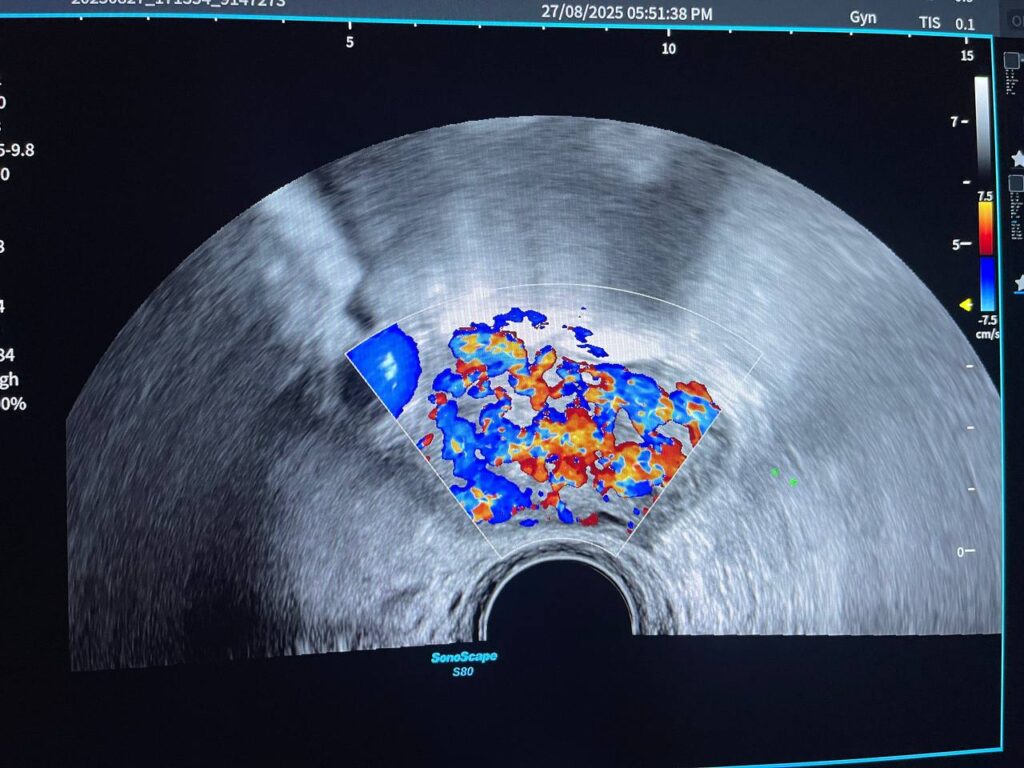

Presence of hyper vascular mass 47x31mm in the right cornua & within the interstitial layer , picture mostly of ectopic H Mole pregnancy , please for further study

Presence of hyper vascular mass 47x31mm in the right cornua & within the interstitial layer , picture mostly of ectopic H Mole pregnancy , please for further study